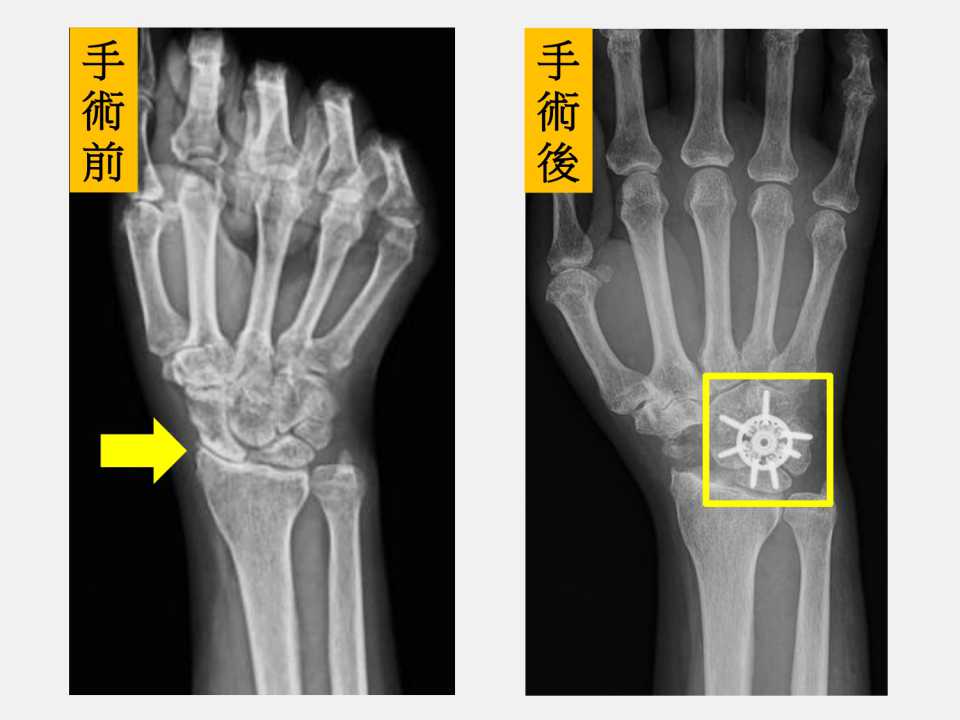

陳重宇醫師表示,傳統的融合術多以鋼釘或螺釘固定,依最新研究顯示,環狀鋼板能提供更佳的初期穩定性,提高骨頭癒合成功率,並讓病人更早開始復健,降低僵硬與肌力流失的風險。由於劉先生的症狀是手腕腫脹、活動受限和握力明顯下降,X光檢查顯示已進展至中後期病程,經醫療團隊充分討論後,劉先生接受「舟狀骨切除合併四角融合術(scaphoid excision and four corner fusion)」,並使用新型環狀鋼板固定,復原順利。